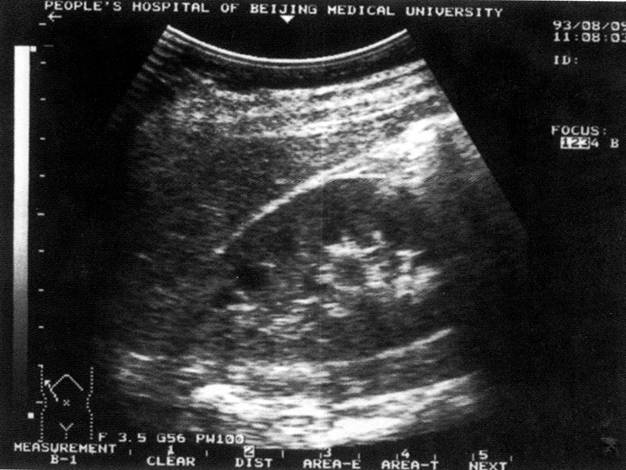

正常肝脏声像图:左图为肝右叶肋间切;右图为肝左叶剑下纵切